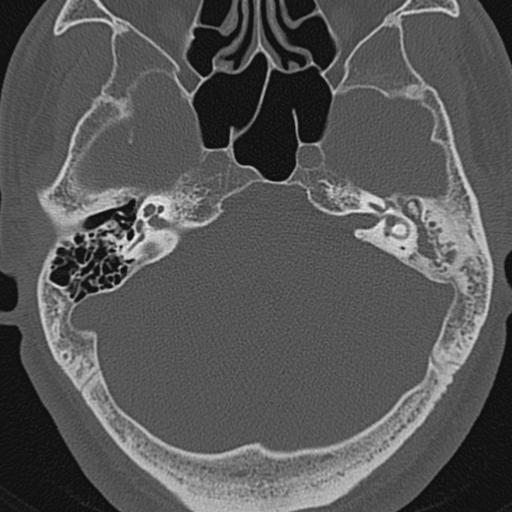

以下是引用zxl51642在2009-8-25 13:37:00的发言:[br]1、左侧慢性硬化型中耳乳突炎(中耳鼓室腔及听小骨受累),并胆脂瘤形成;2、左侧外耳道软组织密度影填塞,考虑炎性肉芽肿,建议结合临床;3、右侧颈静脉窝较左侧明显扩大,不排除颈静脉球瘤,建议mr进一步检查。

以下是引用随光逐影在2009-8-25 19:05:00的发言:[br]1)左侧慢性中耳乳突炎(肉芽肿或胆脂瘤形成),左侧外耳道炎性肉芽肿。2)右侧颈静脉球高位。